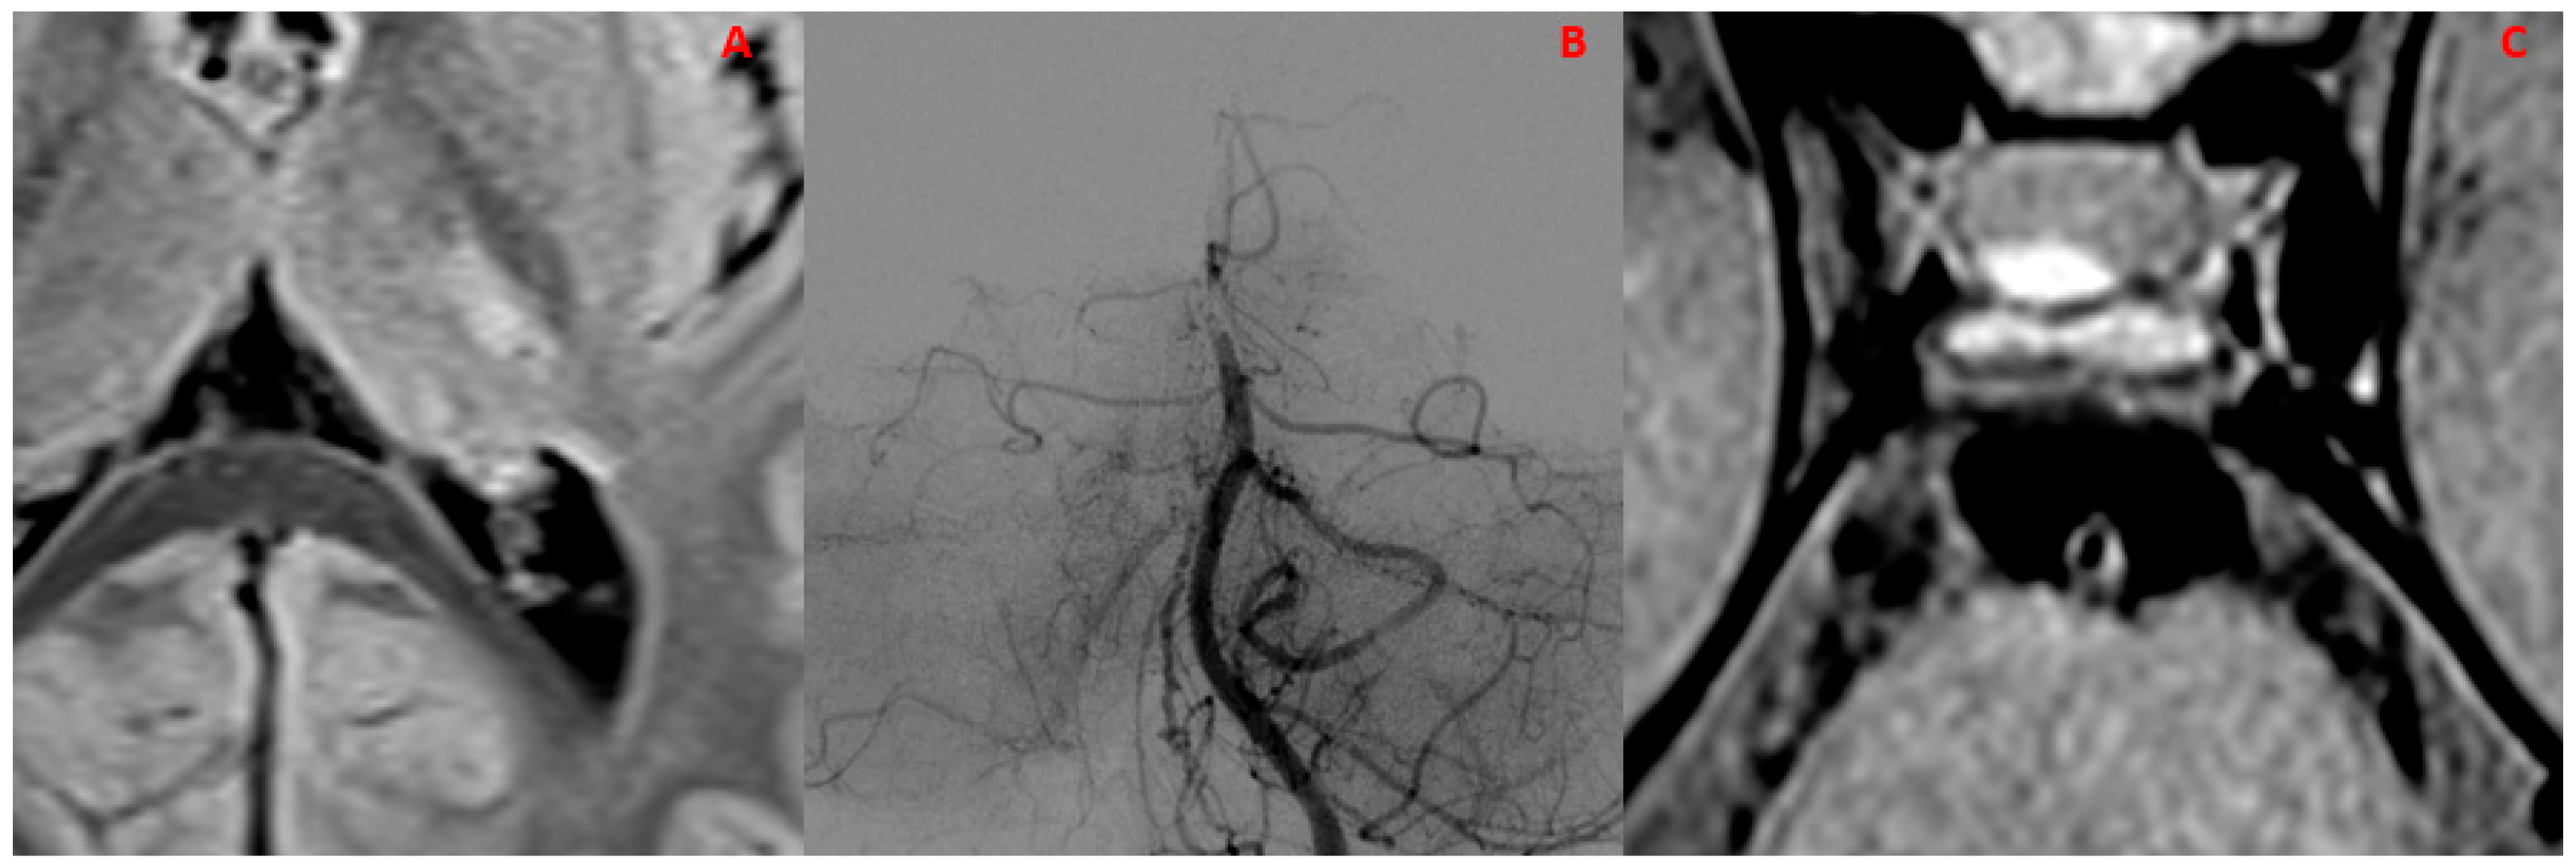

| 5Y, M | Episode suggestive of stroke | (n/a) | Negative | VZV-IgM antibody-positive CRP (+) | (n/a) | VZV-CNSV |

| 5Y, M | // | Absent | Absent | No | VA | BA | Present | Subtentorial |

| 39Y, F | 1 | Absent | Present | No | M1 | PCA (P1) | Absent | // |